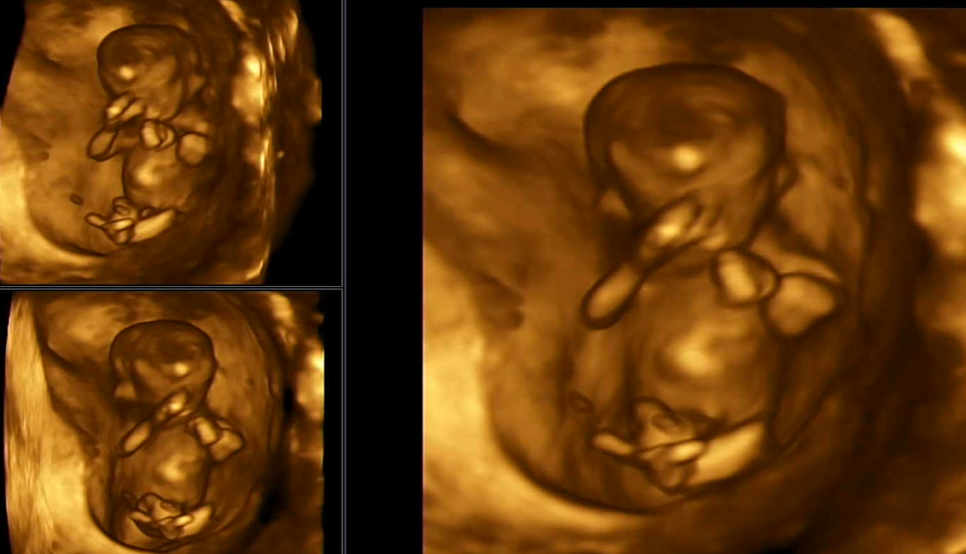

검사 중 킥 실력을 자랑하는 오뜨

안녕하세요~해주는오토,그리고콧날이잘자라있는지확인하는데,이것도다운증후군과관련이있대요.다행히 코뼈도 멋있네요손가락도 5개예요. 이제 뼈가 생겼거든요.손으로 안녕이라고 인사하는 것 같다고 남편이랑 설렌다..ㅋㅋㅋㅋㅋㅋㅋㅋㅋㅋㅋㅋㅋㅋㅋㅋㅋㅋㅋㅋㅋㅋㅋㅋㅋㅋ

1차 기형아 검사 중에 #12주 성별도 한번 봐주셨는데 다리 사이에 뭔가 빠져있는 게 존재감이 뿜뿜이죠?그래서 혹시 아들이신가요? 그러면 탯줄일 수도 있고 손일 수도 있고 저게 없어질 수도 있대.16주가 지나서야 보는게 가장 정확하다고 하더군요!아들이든 딸이든 건강했으면 좋겠어요^^!

손을 얼굴 앞에서 딱 잡고 있는 모습입니다입체 초음파로 보면 역시 두근두근? 보여서 잘 안 보였어요 ㅎㅎㅎ